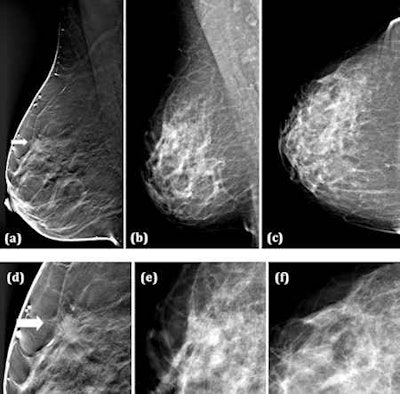

(a) Breast tomosynthesis (BT) mediolateral oblique view (one-view BT), (b) Digital mammography (DM) mediolateral oblique, and (c) DM craniocaudal view (two-view DM), (d-f) close-ups of (a-c). A 49-year-old woman with a 10-mm spiculated invasive tubular carcinoma grade 1. The tumor was detected by 5/5 readers on one-view BT, while on two-view DM (b, c) the tumor was undetected by all the readers. All images courtesy of Tony Svahn, PhD.Svahn's team compared radiologists' ability to detect breast cancers using two-view digital mammography and one-view breast tomosynthesis (Mammomat Novation DR and a tomosynthesis prototype based on this device, both Siemens Healthcare). The prototype breast tomosynthesis system delivered about the same average glandular dose as the two-view digital mammography system, they noted.